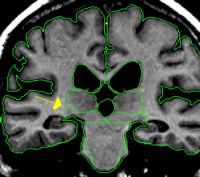

Use the intensity contour function to obtain an outline that tightly hugs the lateral edge of the thalamus but does not exclude any thalamus. This contour will provide most or all of the lateral border of the thalamus and should meet the superior border provided by the caudate or lateral ventricle. Some manual drawing may be necessary, particularly along the ventro-lateral border. This border should never extend to the pallidum. Projection lines should be used in conjunction with sagittal and axial views when boundaries become less clear.

The posterior extent of the thalamus is referred to as the pulvinar. The pulvinar extends posteriorly past the VDC and is located just superior and medial to the hippocampus. In this region the pulvinar is egg shaped and grows smaller as you move to the most posterior extent.